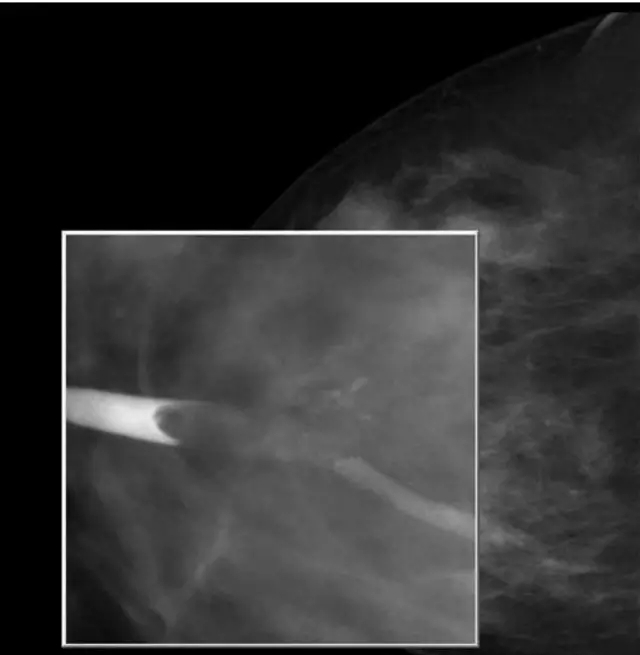

乳腺钼靶检查 什么是钼靶检查?钼靶检查有辐射吗?

钼靶造影检查

随着科学技术的进步,到医院去检查,很多人会被医生要求去做X光、CT,尤其是在我们乳腺科,年龄大于40岁的患者会被要求做钼靶检查,以帮助疾病的诊断。

乳腺钼靶检查又称乳腺摄影,是目前早期监测乳腺癌最有效的办法之一。在钼钯,可以观察到以下:(1)钙化情况,细小、颗粒状、成簇的微钙化点是乳癌的一个重要的早期表现;(2)肿物的形征象态、密度及其边缘征象;(3)有无乳腺结构扭曲?(4)其它征象,如乳头,皮肤,腋窝淋巴结等(5),少量射线,不推荐35岁以下女性检查。